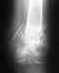

Вот самый свежий снимок, фас и профиль в чуть согнутом положении (но не в крайнем). Также ниже прикреплю компьютерную томограмму. Если этого не достаточно, мы сделаем еще снимки.